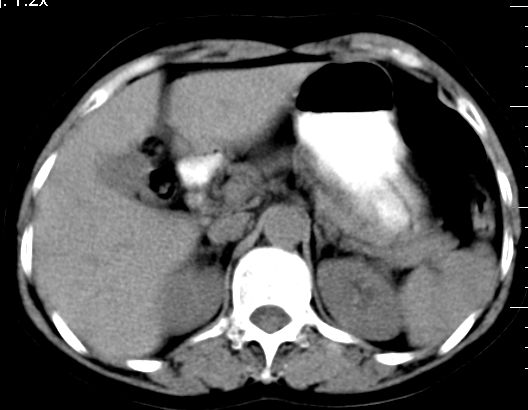

双肾灌注良好,代谢增快,动脉期肾盂见造影剂,左肾下极背侧见一略低密度病灶,延迟期见似不强化囊肿,双侧肾上腺未见异常。

胰腺及脾未见异常。肾门水平腹膜后见小淋巴结。腹腔未见积液征象。

3、左肾下极低密度灶,考虑囊肿可能性大,建议随访,除外小肾癌(无强化可以基本除外)。

左肾下极低密度灶,考虑囊肿可能性大,建议必要时复查

支持;右肝8段小血管瘤,左肾囊肿.